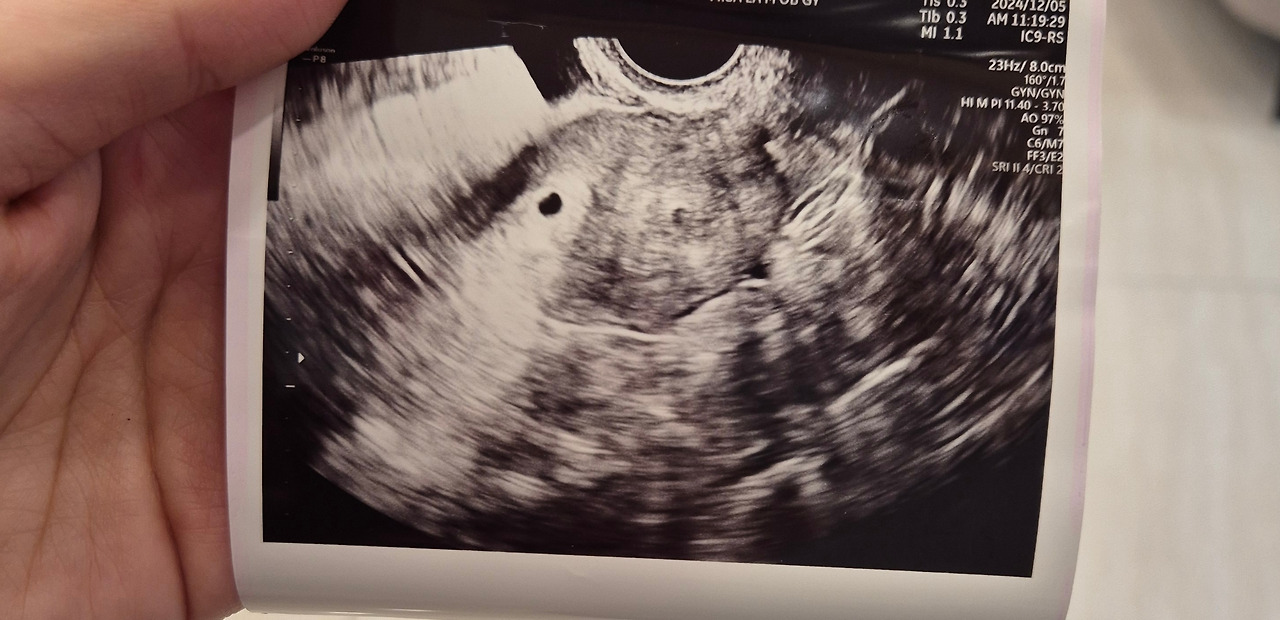

의심스러운 마음으로 병원을 찾았다. 초음파 화면을 보며 의사가 말했다. "아기집이 보이네요." 나는 화면 속 점 하나를 보며 고개를 갸우뚱했다. "그러니까… 진짜 임신이라는 거죠?" 몇 번을 되묻고 나서야 겨우 실감이 났다. 그러니까, 나는 지금 임신 5주 차이고, 내년 8월 8일쯤 아이를 만날 수 있다는 것이다.